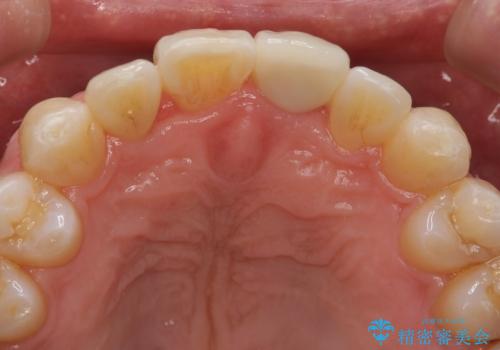

左上1はジルコニアクラウン(スペシャル)で治しました。スペシャルの場合は写真をとり、オリジナルの色味で作成することが可能です。